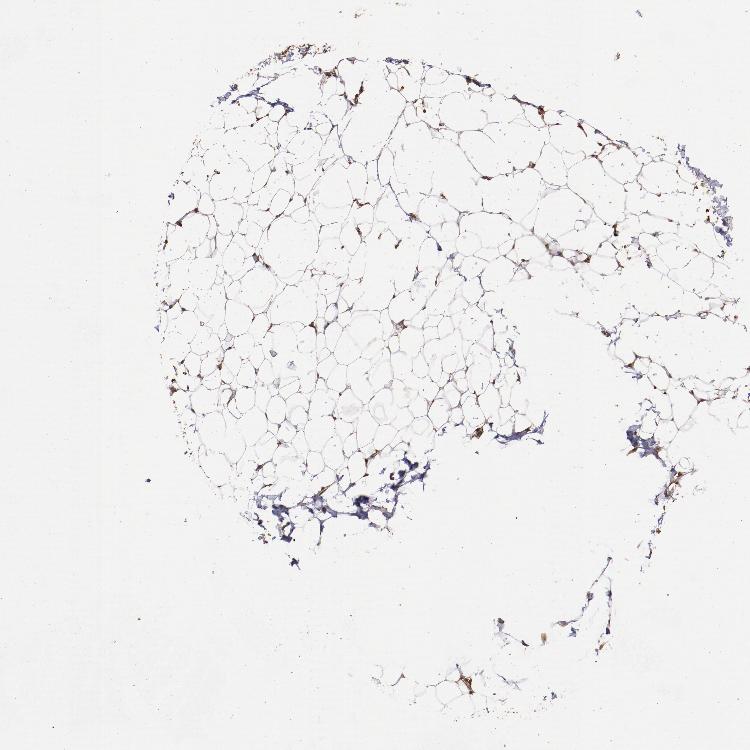

SOFT TISSUE 1 - Antibody stainingi

Antibody staining in the annotated cell types in the current human tissue is reported as not detected, low, medium, or high, based on conventional immunohistochemistry profiling in selected tissues. This score is based on the combination of the staining intensity and fraction of stained cells.

Each image is clickable and will lead to virtual microscopy that enables deeper exploration of all samples and also displays staining intensity scores, fraction scores and subcellular localization as well as patient and tissue information for each sample.

Antibody HPA001619Antibody HPA002078

Chondrocytes Not detected-

Fibroblasts Not detectedMedium